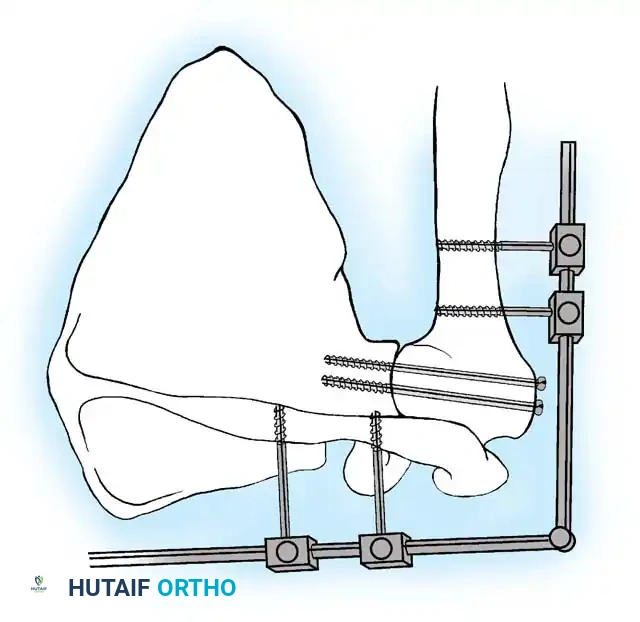

5. Rigid Internal Fixation

The most robust biomechanical construct involves a heavy, malleable plate (such as a 10- to 14-hole 4.5mm pelvic reconstruction plate or a dynamic compression plate). The plate is meticulously contoured to lie flat along the spine of the scapula, bend over the acromion, and extend down the lateral shaft of the humerus.

Screws are placed sequentially:

1. Scapular Spine: Cortical screws are placed into the dense bone of the scapular spine.

2. Acromiohumeral Fixation: Screws are passed through the plate, across the acromion, and into the humeral head.

3. Glenohumeral Fixation: Long, fully threaded cortical or cancellous screws are directed through the plate, through the humeral head, and deep into the glenoid neck and vault. This is the most critical step for achieving compression across the primary fusion site.

4. Humeral Shaft: The distal portion of the plate is secured to the humeral diaphysis.

If additional stability is required, or if bone quality is poor, a second plate (double plating technique) can be applied posteriorly.

Radiographic confirmation of a contoured reconstruction plate achieving rigid acromiohumeral and glenohumeral compression.